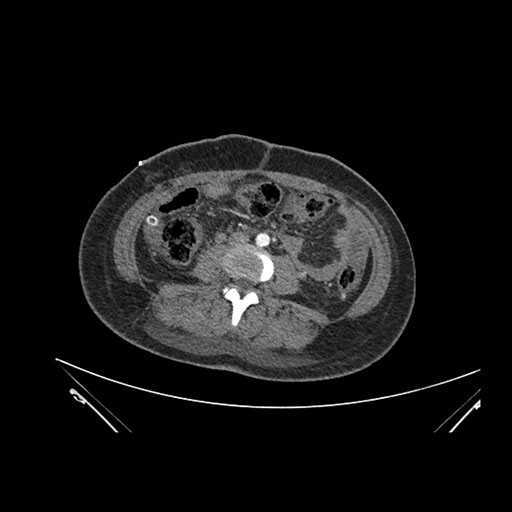

Axial Venous

Imaging analysis

Based on initial findings, which issue(s) would you be most concerned about?